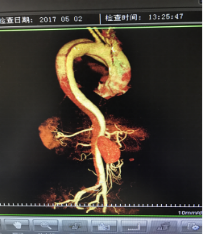

5月2號(hào)劉大伯照常早起干活,突然胸部劇烈疼痛,難以忍受,全身大汗,同時(shí)伴有右上肢發(fā)涼,他心想這次心絞痛比之前嚴(yán)重的多啊,趕緊叫上孩子到吉林國(guó)文醫(yī)院心血管內(nèi)科住院,患者長(zhǎng)期高血壓病史,血壓一直控制不理想,大夫給他做了檢查,測(cè)左上肢血壓:82/45mmHg,右上肢血壓測(cè)不出,心率52次/分,右側(cè)肱動(dòng)脈、尺動(dòng)脈、橈動(dòng)脈搏動(dòng)消失,左側(cè)股動(dòng)脈搏動(dòng)較右側(cè)弱?!霸懔?,雙側(cè)血壓差別這么大,是不是主動(dòng)脈夾層了?”,接診大夫趕緊找來(lái)李主任,李主任反復(fù)詢(xún)問(wèn)患者病情,表情突然凝重起來(lái),患者胸痛這么明顯,血壓低的厲害,主動(dòng)脈夾層的可能性很大。二話不說(shuō),李主任立即聯(lián)系影像科的醫(yī)生準(zhǔn)備做主動(dòng)脈CTA,移動(dòng)患者做檢查的過(guò)程大夫們非常小心,嚴(yán)密監(jiān)測(cè)患者血壓變化情況。兩個(gè)小時(shí)后結(jié)果出來(lái)了,主動(dòng)脈夾層從升主動(dòng)脈一直撕裂到左側(cè)髂總動(dòng)脈?。?!

從開(kāi)始學(xué)醫(yī)到現(xiàn)在已經(jīng)快9年了,主動(dòng)脈夾層患者也見(jiàn)過(guò)一些,但像劉大伯這種危險(xiǎn)類(lèi)型的還是第一次見(jiàn)到,心里真的為他捏把汗,撕裂的主動(dòng)脈隨時(shí)都有可能破裂,生命隨時(shí)可能終止,要知道主動(dòng)脈夾層的死亡率非常的高,約50%的患者發(fā)病后48小時(shí)死亡,約90%的患者發(fā)病1個(gè)月內(nèi)死亡。

李主任詳細(xì)的與劉大伯的女兒交代了病情,手術(shù)是挽救生命的唯一辦法,為了劉大伯的一線生機(jī),我們積極聯(lián)系了我省權(quán)威的心血管外科,并做了詳細(xì)的匯報(bào),兩家醫(yī)院對(duì)此非常重視,為劉大伯開(kāi)通了綠色通道,安全的把他總到上級(jí)醫(yī)院,當(dāng)天便給他進(jìn)行血管置換及覆膜支架植術(shù)。他術(shù)后恢復(fù)的很好,后來(lái)劉大伯的女兒看望我們,感嘆道:沒(méi)想到國(guó)文醫(yī)院心內(nèi)科應(yīng)急能力這么高,在那么短的時(shí)間內(nèi)診斷明確,才給了我的老父親手術(shù)的機(jī)會(huì)。